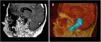

Los schwannomas del nervio glosofaríngeo son tumores de la fosa posterior extraordinariamente raros. En una revisión de 100 años se encontró un total de 42 casos entre 1908-2008. Los datos clínicos más comunes se encuentran asociados a su localización, siendo los más comunes síntomas vestíbulo cocleares y síntomas de afectación de la función del nervio glosofaríngeo. Su diagnóstico actualmente se ha facilitado con el uso de la resonancia magnética; sin embargo, es muy complicado definir en ocasiones preoperatoriamente si el tumor se origina del ix, x u xi nervios craneales. Presentamos el caso de una paciente de 42 años con síndrome del ángulo pontocerebeloso, síndrome del agujero rasgado posterior (yugular) + condileo anterior (Collet-Sicard). El tratamiento empleado fue quirúrgico con abordaje extremo lateral transcondilar, con monitorización de pares craneales y potenciales evocados transoperatorios.

Schwannomas of the glossopharyngeal nerve are extremely rare tumors of the posterior fossa. In a 100-year review, a total of 42 cases were found between 1908-2008. The most common clinical data are associated with its location, the most common being cochlear vestibule symptoms and symptoms of glossopharyngeal nerve function. its diagnosis has now been facilitated by the use of magnetic resonance, however, it is very complicated to define preoperatively if the tumor originates from the ix, x or xi NC. We present the case of a 42-year-old patient with a syndrome of angulopentocerebellar syndrome, posterior torn (jugular) hole syndrome + anterior condyle (Collet-Sicard). The treatment used was surgical with transcondylar lateral extreme approach, with monitoring of cranial nerves and trans-operative evoked potentials.